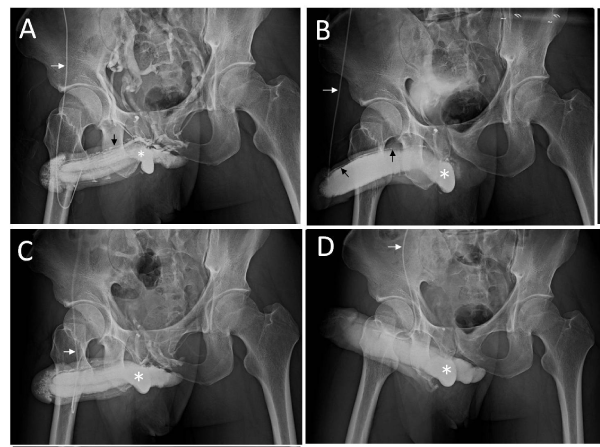

| Figure 2: Data obtained during dual cavernosography. A). The cavernosograms was taken while Omnipaque solution profuse the corpora cavernosa (asterisk) via a #19 scalp needle (white arrow). This film shows the deep dorsal vein (black arrow) as well as the cavernosal vein (masked). B). After the intracavernous injection of 20μg prostaglandin E1 (test), a pharmacocavernosogram demonstrates veno-occlusive dysfunction (VOD) because the leaky veins (black arrows) still present. The ventral curvature is remarked. C). This film was obtained after surgery with the similar condition as that in panel A. Note the sinusoids (asterisk) was obviously improved in fluid retention. D). Similarly it is for comparison with panel B. Note no more leaky veins and penile dysmorphology. Thus an ideal penile shape is there. |